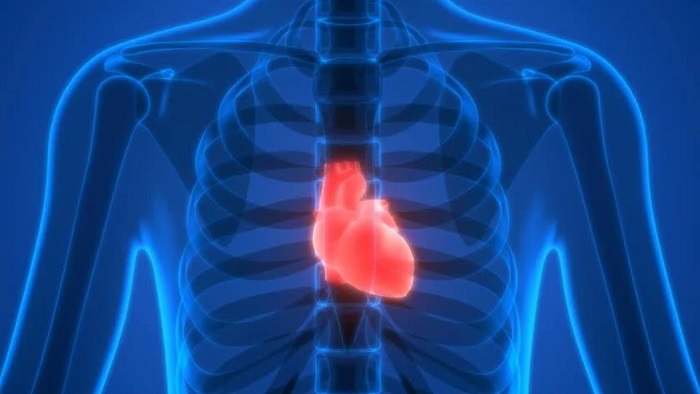

A heart attack is a medical emergency that occurs when the heart stops working properly. A myocardial infarction, which is another name for a heart attack, occurs when the heart’s muscle doesn’t receive enough oxygen-rich blood. Without treatment to restore blood flow, the damage to the heart muscle increases over time.